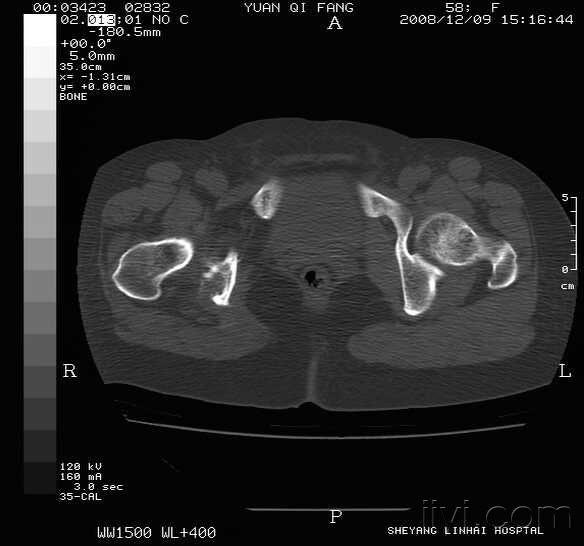

髋关节ct请各位看看!

髋关节CT

正常髋关节ct

髋关节ct图片

髋关节ct解剖图